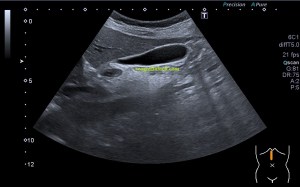

Durante la exploración de una eco de abdomen en el contexto de un paciente que acude por elevación de transaminasas observo una imagen heterogénea, irregular, con una pared marcadamente calcificada, bilobulada de gran tamaño que medí en dos partes ya que me pareció claramente que estaban diferenciadas.

Una de ellas, la primera, era mucho más hiperecogénica y más pequeña, su centro estaba mas calcificado, su sombra acústica posterior era mucho más acuciada y llamaba más la atención. Justo al lado, otra lesión de mayor tamaño, su calcificación era mucho más sutil y más periférica delimitando una LOE hipoecogénica de un tamaño muy importante, adyacente a la más pequeña, como he comentado previamente. Ambas sin señal Doppler.